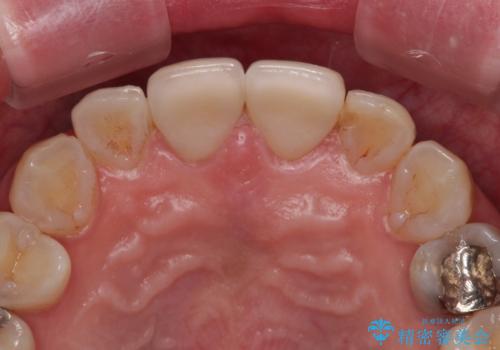

- つぎはぎのある前歯のセラミックの色合いが気になるとのことで来院された患者様です。

グレーの色が透けて見える気がする点が気になっていらっしゃり、やや黄色みのある色を希望されていました。

仮歯に置き換えた後にオールセラミッククラウンにて補綴治療を行うこととしました。